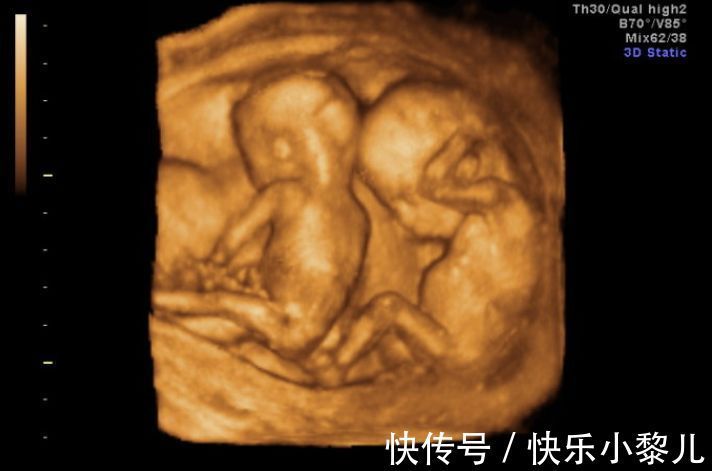

▼ 可能是怀了多胎没检查出来

一些孕妇怀孕后去医院检查,医院的设备可能没有检查出,孕妇肚子里的胎儿是双胞胎或多胞胎的情况,家里人也不知道,多胎的肚子自然比单胎更加显怀,显着肚子更大。